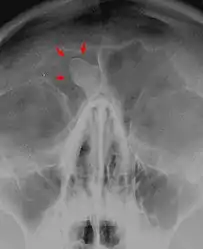

Medical imaging such as X-ray, CT scan and MRI show dense, clearly defined, round white tumors attached to bone.[1] They can be left alone if not troubling, and surgically cut out if pressure symptoms.[1] The surgery may be possible through the nose, without making a large cut.[3]

Medical imaging such as X-ray, CT scan and MRI show dense, clearly defined, round white tumors attached to bone.[1] They may be diagnosed when having medical imaging for another reason.[3] Osteomas of the paranasal sinuses and skull base can be diagnosed using CT-scan without intravenous contrast, allowing its size and relation to nearby important structures to be assessed.[3] A biopsy is not usually required.[3]

X-ray skull: Osteoma of the frontal sinus